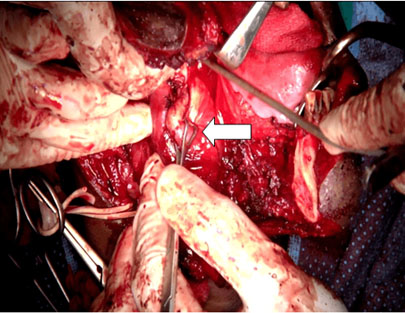

After all routine investigations, the patient was planned for right parapharyngeal tumor excision via combined cervical and mandibular swing approach under general anesthesia. Horizontal skin crease incision was given 2 inches below right lower border of mandible and extended anteriorly to split lower lip in midline. Incision was extended intraorally along right gingivobuccal sulcus to right anterior tonsillar pillar and soft palate. Subplatysmal flaps were elevated superiorly and inferiorly exposing the tumor. Right facial vessels were identified, secured, and divided. Right submandibular gland was excised. Carotid sheath was incised and carotid control was achieved. Mandibulotomy was done (Figure 5). Lingual and hypoglossal nerves were identified and preserved (Figure 6). The right parapharyngeal tumor was dissected in toto (Figure 7). Mandibular osteotomy was fixed with plates and screws and wound was repaired in layers. There was no significant intraoperative bleeding. Ryle’s tube was inserted. Post-operative period was uneventful.

Figure 5: Tumor (white arrow) being dissected out from parapharyngeal space via combined transcervical and mandibular swing approach.